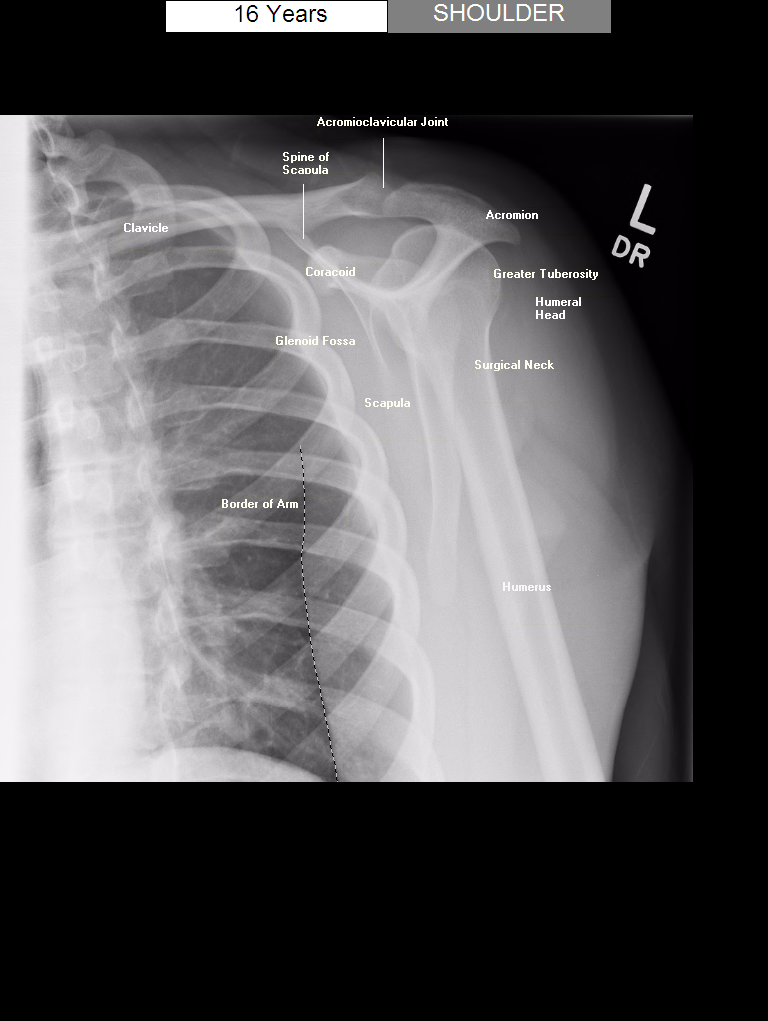

7. "Y" view는 무엇인가?

"Y" view는 어깨의 특수한 방사선 영상으로, 상완골두를 견봉과 오훼돌기 둘 사이에 위치시켜 Y 형태를 하게끔 하여 보여주는 사진이다. 이 영상은 상완골두와 관절와의 상대적인 위치를 측정하는 데 도움을 주며, 어깨 관절(관절와상완관절)의 탈구를 진단하는 데 도움을 준다.

△ Shoulder Y View (이미지 출처 : www.pedxray.com)